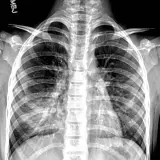

Over 2,100 interactive radiology cases, curated by radiologists for your level of training. Scroll, window, and view cases full screen — just like on PACS. Click linked findings in each writeup to jump straight to them on the image. Cases include sample reports, a focused discussion section, original illustrations, and videos.

PACSで期待されるツールを完備した完全インタラクティブな症例 — スクロール、ウィンドウ調整、ズーム、パン、計測、ROI、フルスクリーンモード。

重要な所見を症例画像上に直接ハイライトする豊富なアノテーション。症例解説内のリンクされた所見をクリックすると、スキャン上の正確な位置へジャンプできます。

アノテーション付きの画像所見とイラストで効率的に学習